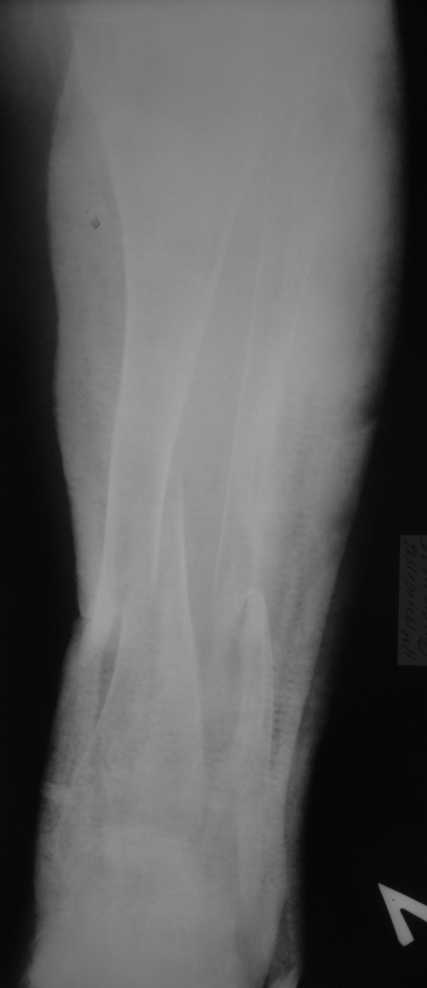

Но даже при малоинвазивной методике лечения применимой для даной больной существуют следующие проблемы: выраженный остеопороз, тонкий кортикал, очень широкий канал.

Контрольные рентгенограммы прилагаю.

Проблема в том, что в сагитальной плоскости угол голеней =30 градусам. Ширина канала 30.

Судя по Ro-граммах у больной скорее всего Vit-D

резистентный рахит и его последствия.Имеем наблюдения лечения остеопороза у данного контингента больных активными формами Vit-D -кальцитриол,даже в таком возрасте (положытельные результаты уже через 1-2 мес.).Фиксация фрагментов возможна внеочеговым аппаратом (самонарезные стержни в аппарате Илизарова).